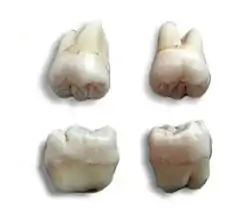

Morphology of wisdom teeth can be variable.

Maxillary (upper) third molars commonly have a triangular crown with a deep central fossa from which multiple irregular fissures originate. Their roots are commonly fused together and can be irregular in shape.

Mandibular (lower) third molars are the smallest molar teeth in the permanent dentition. The crown usually takes on a rounded rectangular shape that features four or five cusps with an irregular fissure pattern. Roots are greatly reduced in size and can be fused together.[8]